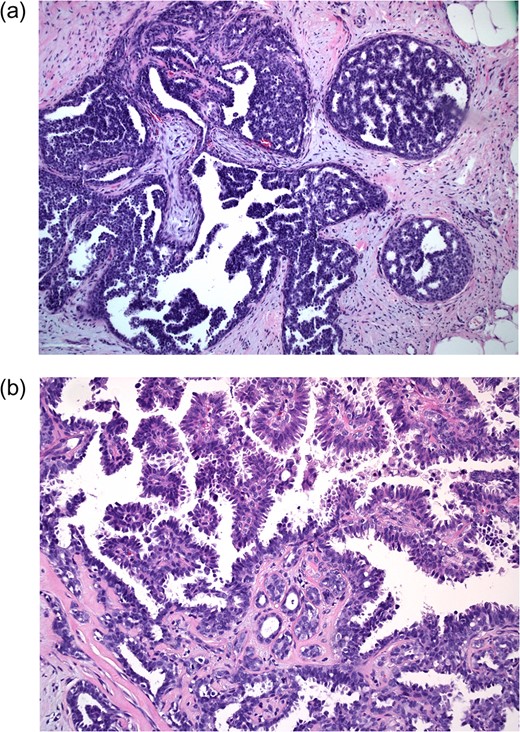

The pathology showed pure micropapillary and cribriform type low-grade DCIS with no evidence of invasive disease (Fig. 3). Breast specific gamma imaging (BSGI) and genetic testing for BRCA gene mutations were ordered. BRCA testing was negative for both BRCA1 and BRCA2 mutations. The BSGI revealed minimal parenchymal activity in the bilateral breasts, however, an area with vague radiotracer activity in a 2.5 cm diameter region was seen that was consistent with the biopsy location. After discussing the diagnosis and treatment options with the patient, he strongly desired bilateral mastectomy. After further discussions with other breast surgeons and a medical oncologist, simple left and right mastectomy with sentinel node biopsy on the left were offered to the patient.

Excisional biopsy at 10× magnification (a) shows neoplastic cells within ducts; 20× magnification (b) demonstrates cribriform and micropapillary features (samples stained with hematoxylin and eosin).